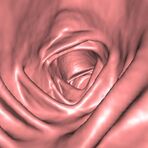

• Virtuelle Kolonographie zur Darstellung des Dickdarmes z. B. bei Kontraindikation zur Darm-Spiegelung oder nur unvollständig durchführbarer Koloskopie.